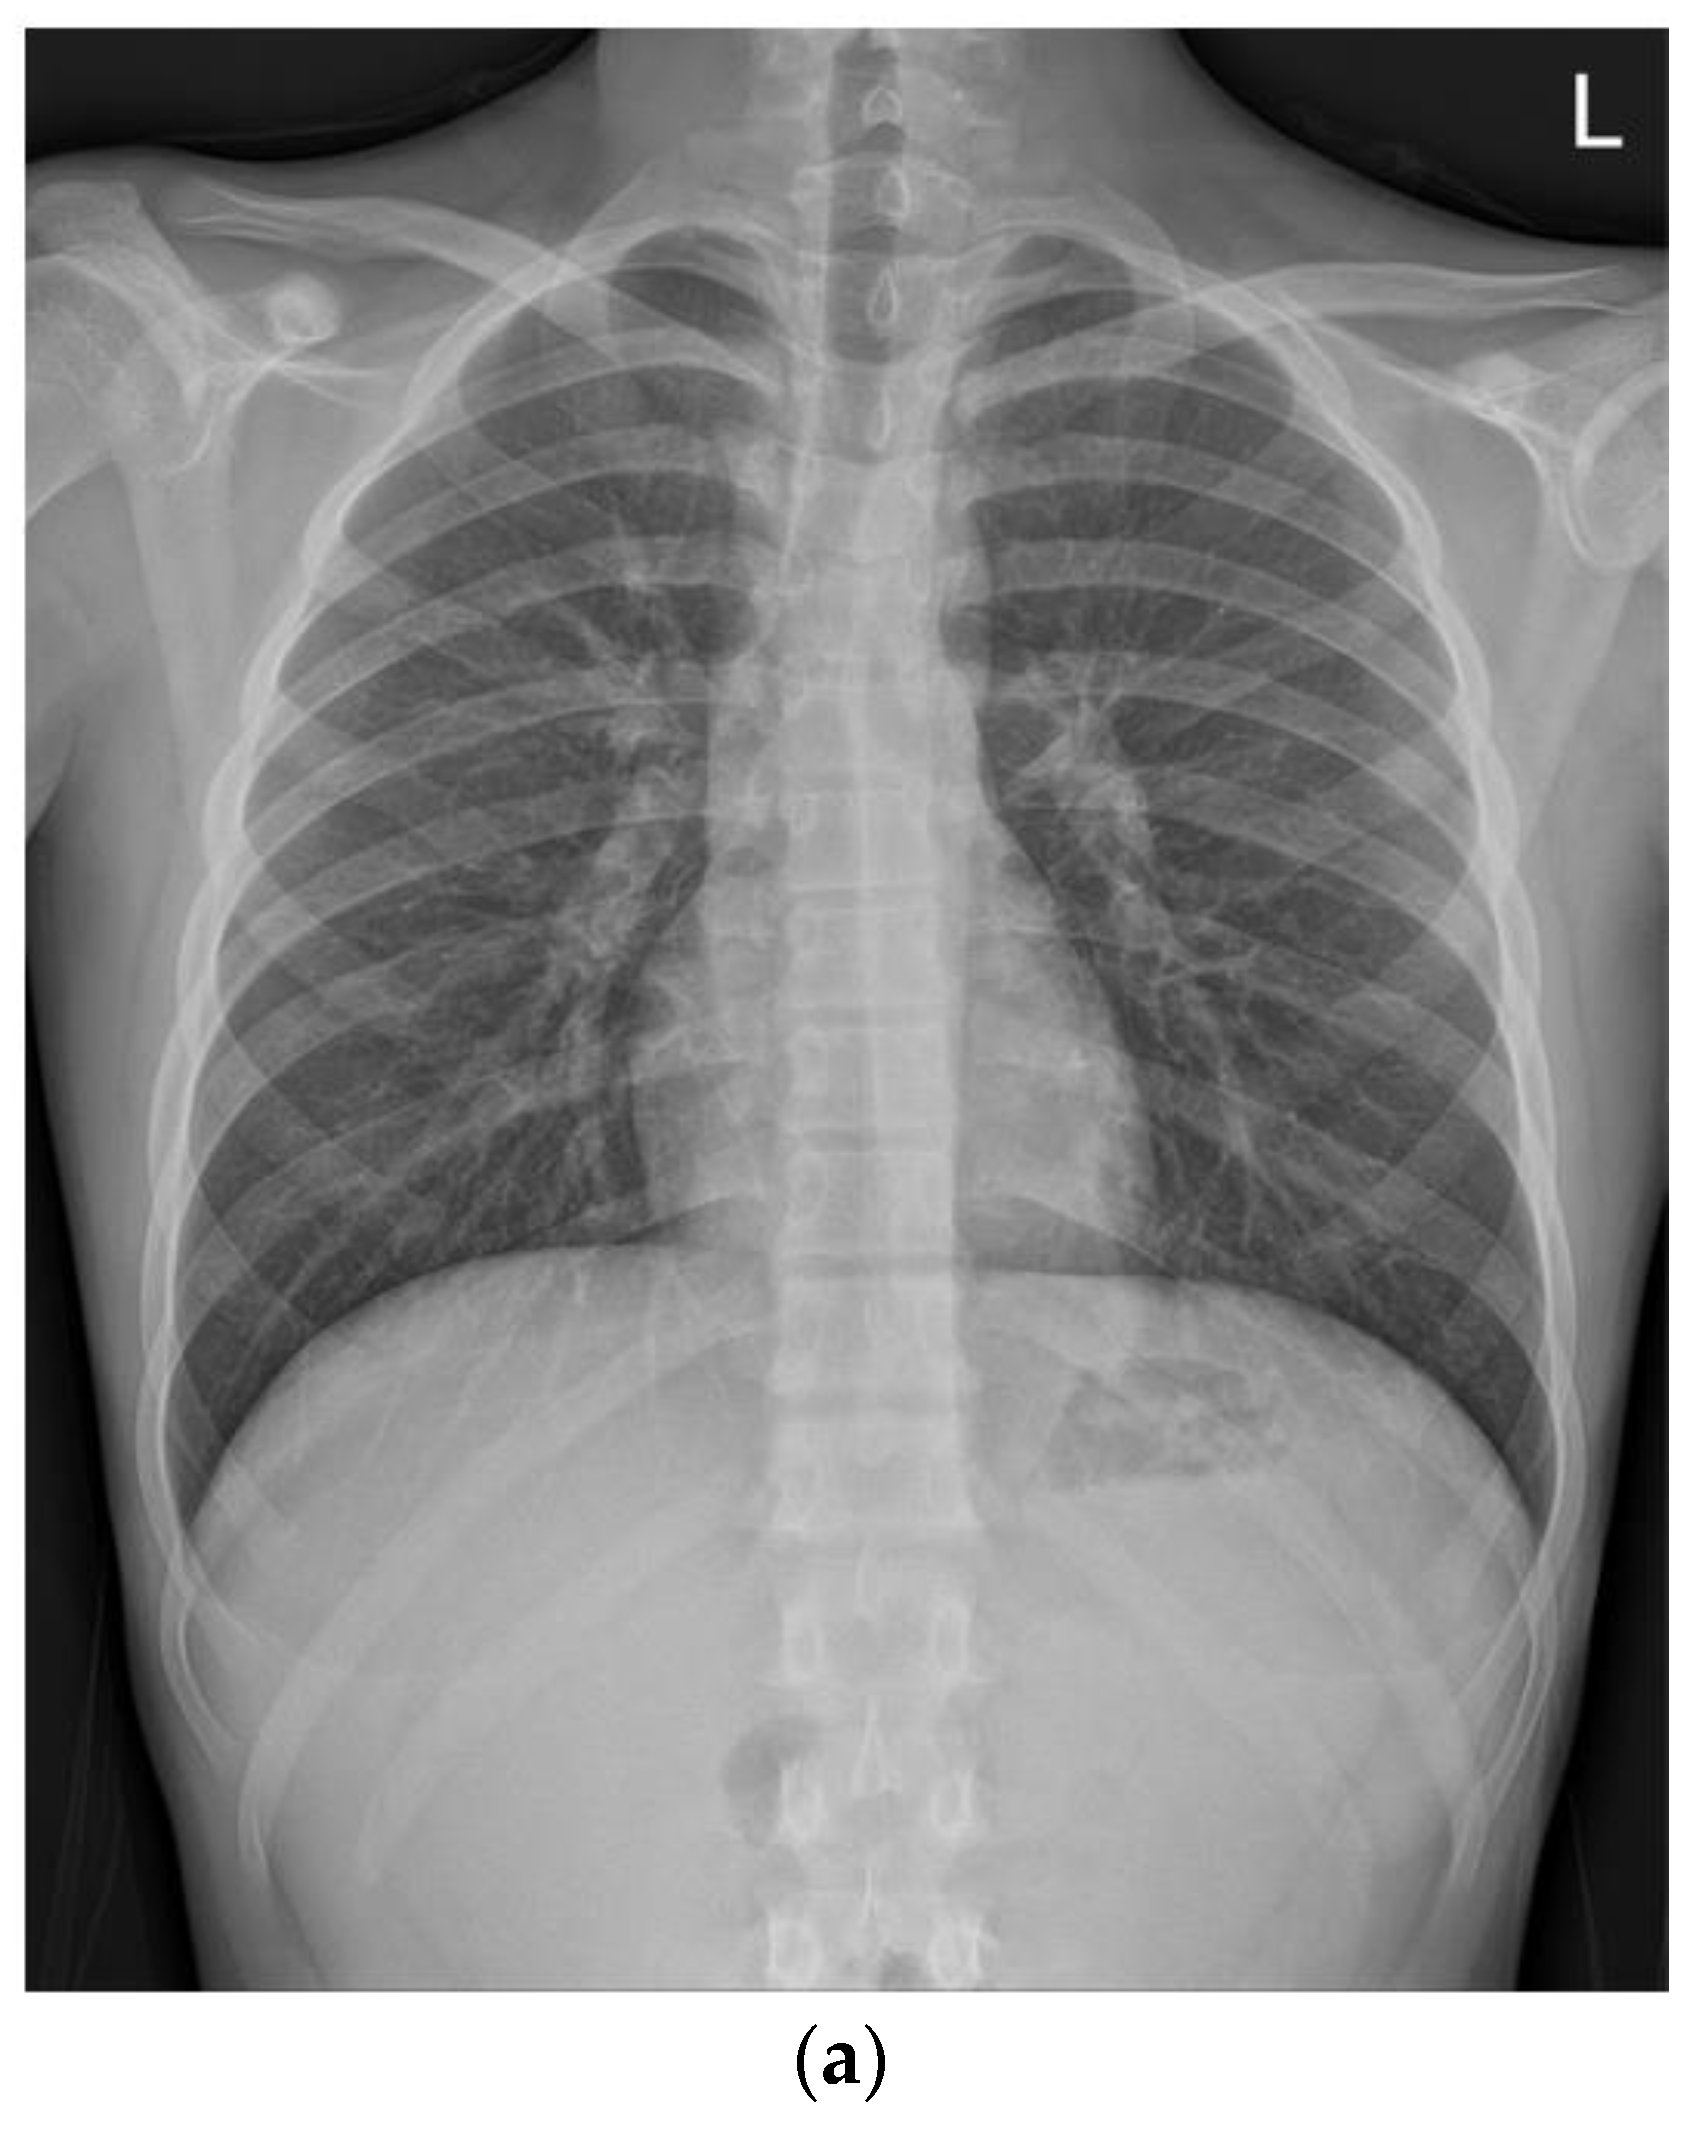

On the second day of hospitalization, he complained of dizziness, chest discomfort, and dyspnea before magnetic resonance (MR) enterography and endoscopy were performed. Vital signs were unstable; blood pressure was 80/60 mmHg, heart rate was 128 beats/min, respiratory rate was 30/min, body temperature was 36.4 °C, and oxygen saturation was 80%. Arterial blood gas analysis revealed a pH of 7.5, pCO2 of 31, and HCO3 of 24.2. Chest radiography and CT revealed pulmonary edema and cardiomegaly (Figure 1).

Figure 1.

Compared with the chest radiography (a) at the time of admission, the chest radiography (b) and low-dose chest computed tomography (c) performed on the second day of hospitalization revealed pulmonary edema and cardiomegaly findings (b).